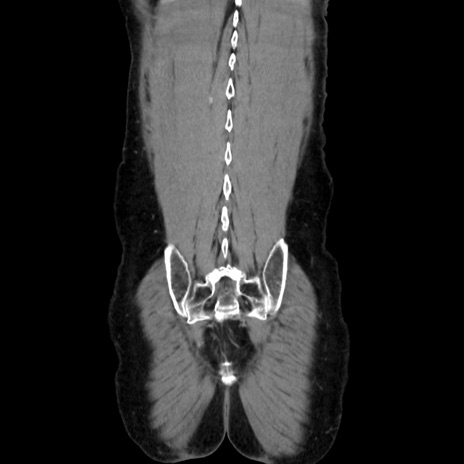

症例37(冠状断像)

【症例】40歳代 男性

【主訴】腹痛

【現病歴】4時間ほど前に電車に乗車中に臍部上より腹痛出現。徐々に増悪し起立困難となり、救急外来受診。生ものは数日食べていない。今朝お雑煮を食べた。

【身体所見】BT 36.8℃、BP 117/84mmHg、HR 91/min、SpO2 97%、苦悶様、腹部:臍上部広範囲圧痛あり、反跳痛±

【データ】WBC 8100、CRP 0.03